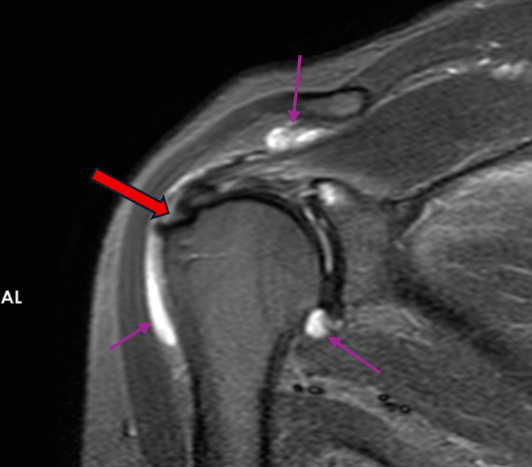

肩袖损伤在MRI图像上的表现

肩袖由冈上肌、冈下肌、肩胛下肌和小圆肌的肌腱共同构成,形似袖套包裹肱骨头。正常情况下,肌腱在MRI图像上呈现为均匀的低信号(黑色)。当发生损伤时,可能表现为肌腱增粗、连续性中断、信号异常,在压脂序列上信号增高(白色)。

图1-2.正常肌腱表现为黑色(橙色箭头所示)

冈上肌肌腱滑囊侧部分撕裂,伴滑囊、关节囊积液(紫色箭头所示)

冈上肌腱完全撕裂,肌腱挛缩(白色,深红色箭头所示)